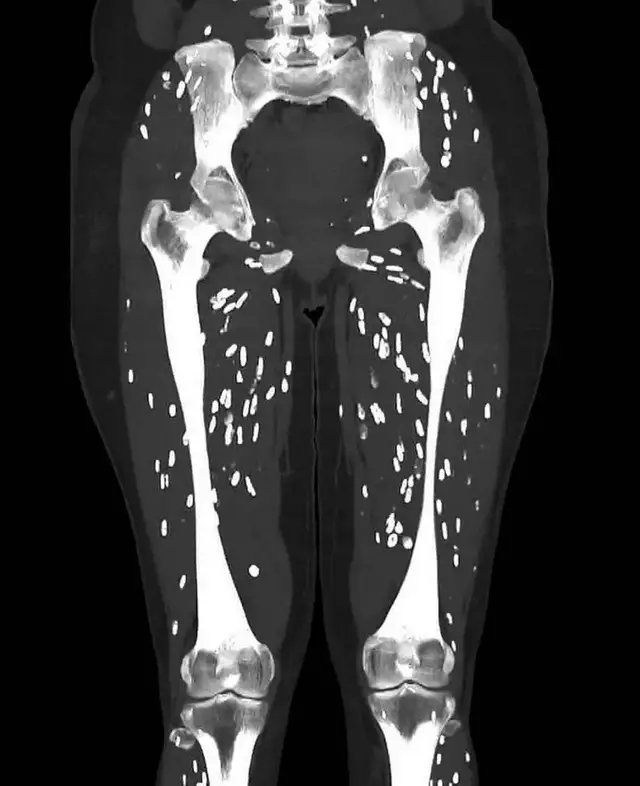

Eating undercooked pork is a serious health risk that can lead to a parasitic infection called cysticercosis. This happens when the larvae of a pork tapeworm enter the body’s tissues, forming hard lumps that resemble rice grains on medical scans.

While these “rice grain” bumps are often harmless in muscle tissue, the situation becomes dangerous if the larvae reach the brain. This condition, known as neurocysticercosis, is a leading cause of seizures and epilepsy worldwide. It can also cause severe headaches, confusion, and even fatal brain swelling.

The infection is primarily spread through the ingestion of tapeworm eggs. This often occurs when people consume undercooked pork or through poor hygiene, such as not washing hands properly after using the bathroom. Once swallowed, the eggs hatch and the larvae penetrate the intestinal wall to travel to the brain, eyes, and muscles.